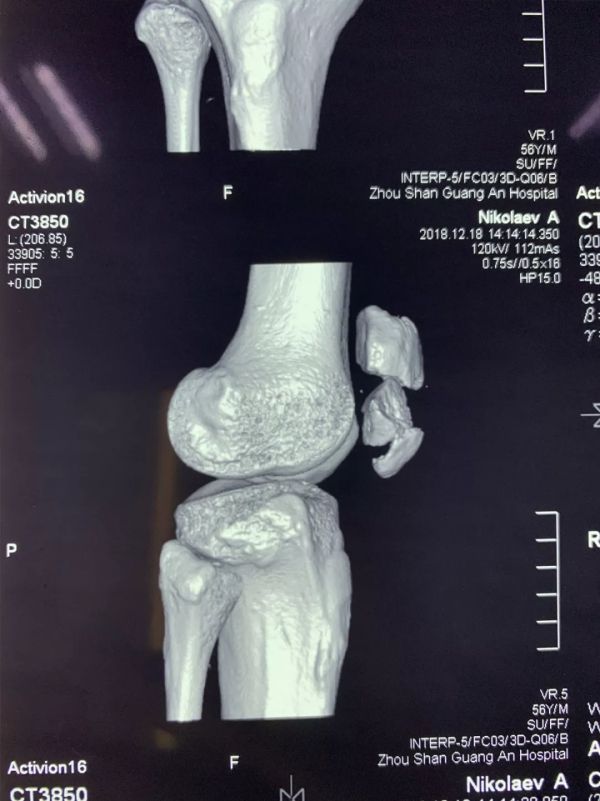

近日,廣安醫(yī)院關(guān)節(jié)科羅軍主任帶領(lǐng)科室團(tuán)隊(duì)成員為一名來自俄羅斯的患者成功施行了右髕骨粉碎性骨折切復(fù)內(nèi)固定手術(shù)治療,術(shù)后三天患者能自行起床活動(dòng)。

患者從遙遠(yuǎn)的俄羅斯來到美麗的舟山群島船廠指導(dǎo)工作,旅途中不慎跌倒,導(dǎo)致右髕骨粉碎性骨折,需行手術(shù)治療,患者來到廣安醫(yī)院就診,然而語言不通,患者只能聽懂簡單的英文,怎么辦?機(jī)智的易觀俊主治醫(yī)師用手機(jī)上的翻譯軟件,搭好了醫(yī)患溝通的橋梁。